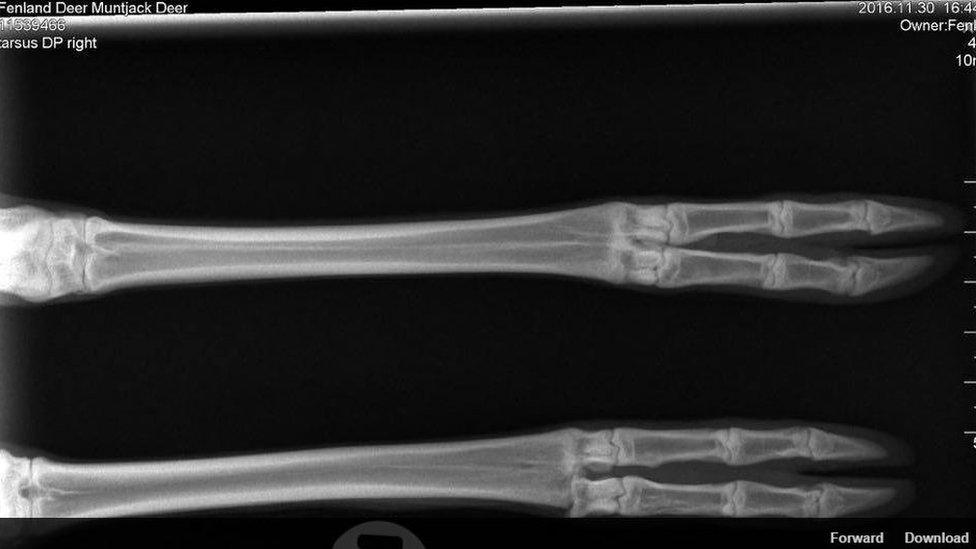

The deer suffered a dislocated ankle

A scan found the animal had suffered lacerations and a dislocated ankle but also that she was heavily pregnant. The centre said on Sunday morning the doe had given birth overnight.